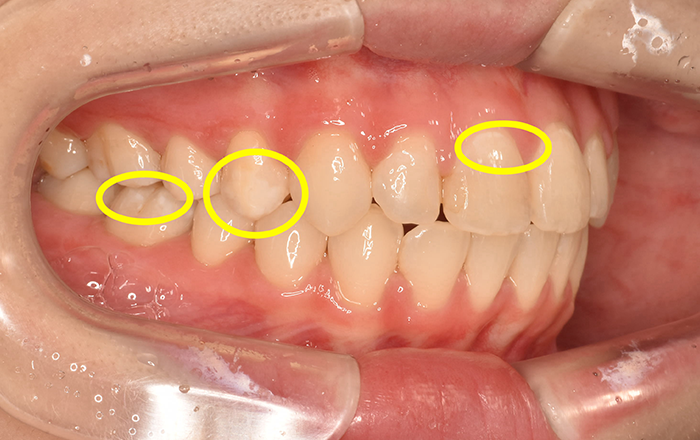

この歯にできる白い斑点の模様のことをホワイトスポットと呼びます。

2つ目の原因は…エナメル質形成不全症と言われるものです。

簡単に言うと、エナメル質形成不全は、歯の表面にあるエナメル質がうまく形成できていない状態です。これは遺伝で起こったり、歯の発育段階のときに外傷を受けたり、乳歯に大きな虫歯ができた影響が永久歯にまでおよび、エナメル質形成不全が起きることがあります。

エナメル質形成不全の場所は虫歯にもなりやすい上に、虫歯の進行も早いです。